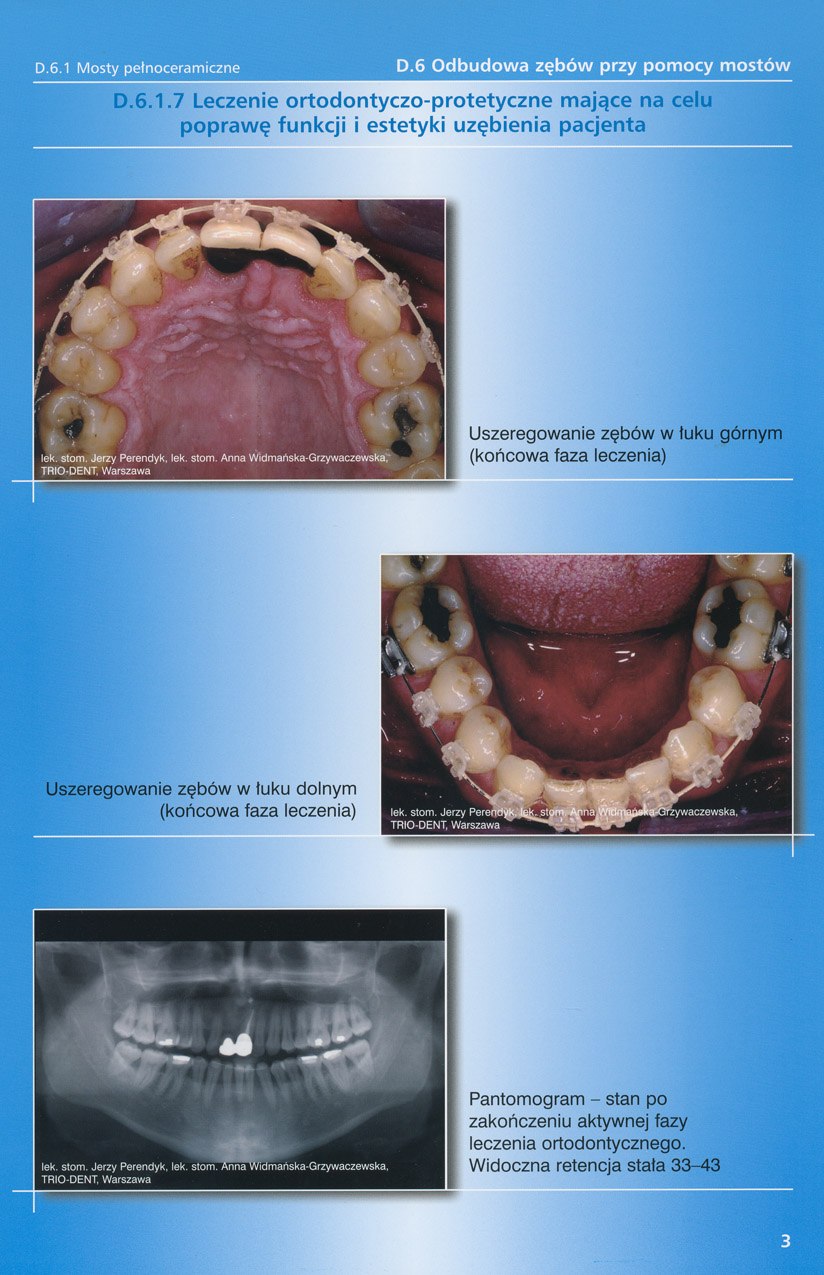

zobacz więcejGaleria przypadków klinicznych, obrazująca proces terapeutyczny od stanu wyjściowego aż do oddania ostatecznej pracy uzupełnienia brakującego uzębienia.